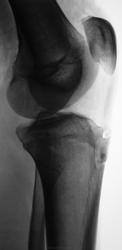

Пациент направлен на рентгенографию коленного сустава.

А сколько пациенту лет? По-моему пациент не молод. Не похоже ли на Осгуд-Шляттера?

Пациенту 16 лет.

Я посчитала, что есть субхондральный склероз в б\б кости, поэтому решила, что не молод. Тогда все-таки Шляттера

Какой красивый Осгуд-Шляттерyes. Скорее всего будет негоден.

Осгуд-Шляттер

остеохондропатия бугристости

А чем объясните зону уплотнения структуры большой берцовой кости на уровне головки малой берцовой кости?

Неоднозначно всё